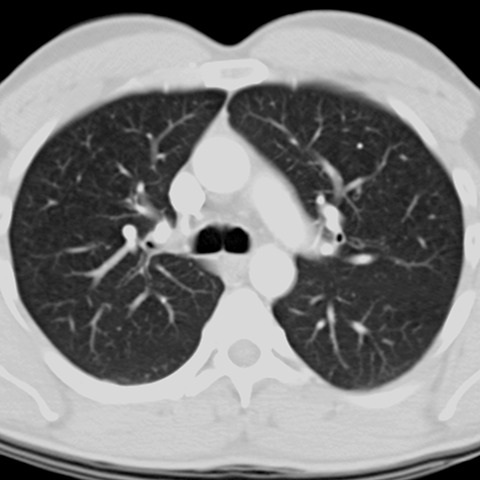

Normal Contrast-Enhanced CT (Lung Window) [5 of 8]